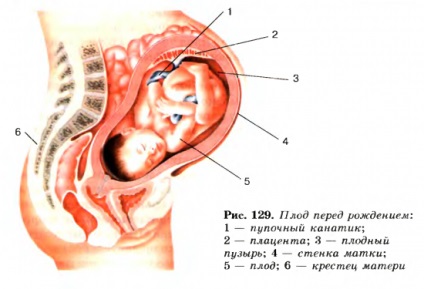

A magzat már a születés előtt

37 hetes kisgyermek olyan jelek megszületni készült. Ebben az időszakban, a baba már egy teljesen egyedülálló személy, aki rendelkezik:

- képződött arcvonásait;

- rajz a bőrön;

- körmök

- szőr;

- keményített fül és nazális porcok.

Mi történik az anya teste

A tizedik héten a terhesség, a várandós anya valóban kész a jövőbeli szállítás, amint azt egy jelentős számának növekedése generált vernix. Belül 37 hetes, általában akkor fordul elő hasi ptosis, és elkezdődhet, képzési viadal. Szigorúan véve ezek kezdenek korábban, de ez az időpont egyre gyakoribbá. Normális esetben legyen fájdalommentes és rendszertelen.